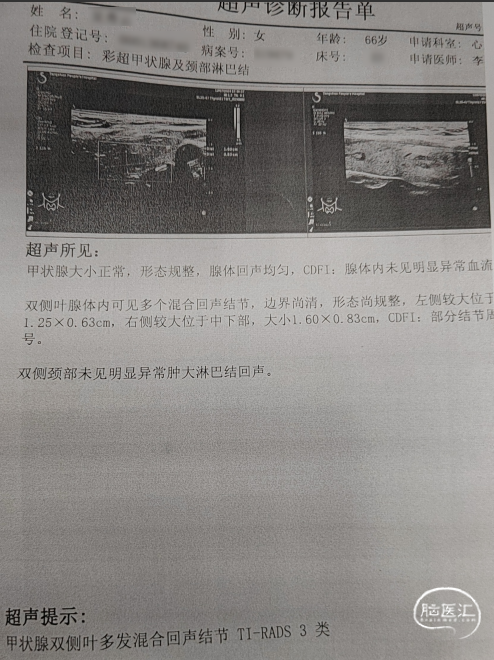

· 于我院查颈部血管超声示“双侧颈动脉内-中膜增厚伴多发斑块形成;左侧颈内动脉闭塞可能,建议超声造影;左侧颈外动脉起始处狭窄,狭窄率70-99%;右侧锁骨下动脉起始处斑块形成”。查头颈部血管CTA示“主动脉弓及弓上大血管动脉粥样硬化表现,左侧颈内动脉颈段至破裂孔段闭塞;左侧锁骨下动脉起始部中重度狭窄”。

头颈部CTA影像及报告(2024-07-24)。

入院头颈部CTA影像及报告(2024-09-05)。